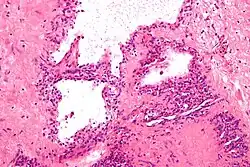

| Micrograph showing a pancreatic serous cystadenoma, a type of cystadenoma. H&E stain. | |

Cystadenoma is a type of cystic adenoma. When malignant, it is called cystadenocarcinoma.